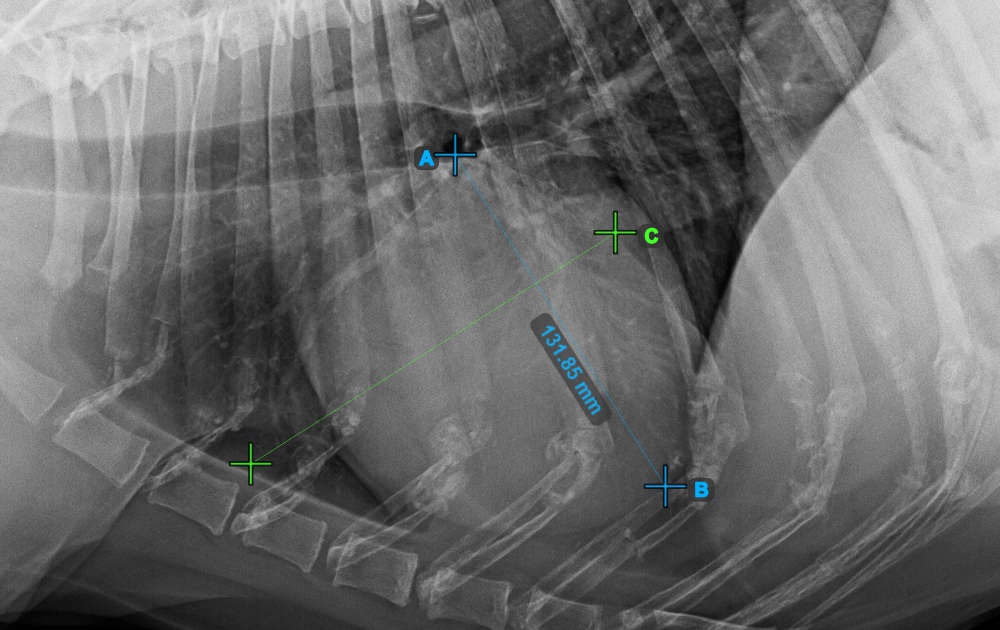

Indítsa el a mérést a Bifurcatio tracheae megjelölésével, a szív felső részéhez közel.

Az alábbi kép a Bifurcatio tracheae pont tipikus elhelyezkedését mutatja.